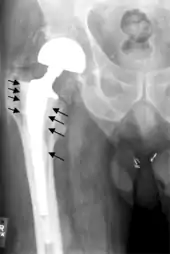

Osteolysis

Many long-term problems with hip replacements are the result of osteolysis. This is the loss of bone caused by the body's reaction to polyethylene wear debris, fine bits of plastic that come off the cup liner over time. An inflammatory process causes bone resorption that may lead to subsequent loosening of the hip implants and even fractures in the bone around the implants. In an attempt to eliminate the generation of wear particles, ceramic bearing surfaces are being used in the hope that they will have less wear and less osteolysis with better long-term results. Metal cup liners joined with metal heads (metal-on-metal hip arthroplasty) were also developed for similar reasons. In the lab these show excellent wear characteristics and benefit from a different mode of lubrication. At the same time that these two bearing surfaces were being developed, highly cross linked polyethylene plastic liners were also developed. The greater cross linking significantly reduces the amount of plastic wear debris given off over time. The newer ceramic and metal prostheses do not always have the long-term track record of established metal on poly bearings. Ceramic pieces can break leading to catastrophic failure. This occurs in about 2% of the implants placed. They may also cause an audible, high pitched squeaking noise with activity. Metal-on-metal arthroplasty releases metal debris into the body raising concerns about the potential dangers of these accumulating over time. Highly cross linked polyethylene is not as strong as regular polyethylene. These plastic liners can crack or break free of the metal shell that holds them.

Loosening

On radiography, it is normal to see thin radiolucent areas of less than 2 mm around hip prosthesis components, or between a cement mantle and bone. However, these may still indicate loosening of the prosthesis if they are new or changing, and areas greater than 2 mm may be harmless if they are stable.[21] The most important prognostic factors of cemented cups are absence of radiolucent lines in DeLee and Charnley zone I, as well as adequate cement mantle thickness.[22] In the first year after insertion of uncemented femoral stems, it is normal to have mild subsidence (less than 10 mm).[21] The direct anterior approach has been shown to itself be a risk factor for early femoral component loosening.[23][24][25]